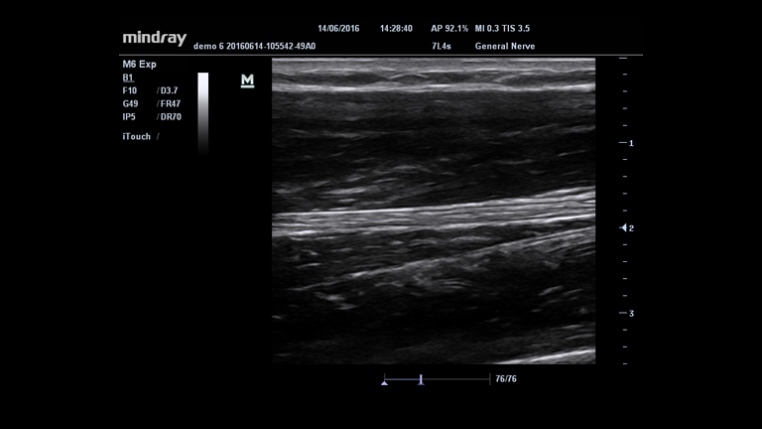

???? ?? ??? ?? ?? ??? ??? ?? ?? ?? ???? ???? ?? ????? ?? ??? ??? ?????. ??? ???? ??? ???? ?? ??? ?? ??? ?? ?? ??? ?? ???? ?? ?????? ??? M6? ??????, ? ???? ?? ? ?? ?? ??? ???? ??? ??? ??? ?? ???? ???? ?????.

??? ??? ?? ?? ?? 8?? ?? ??, ??? ?? ???? ?? ?? ??? ?????.